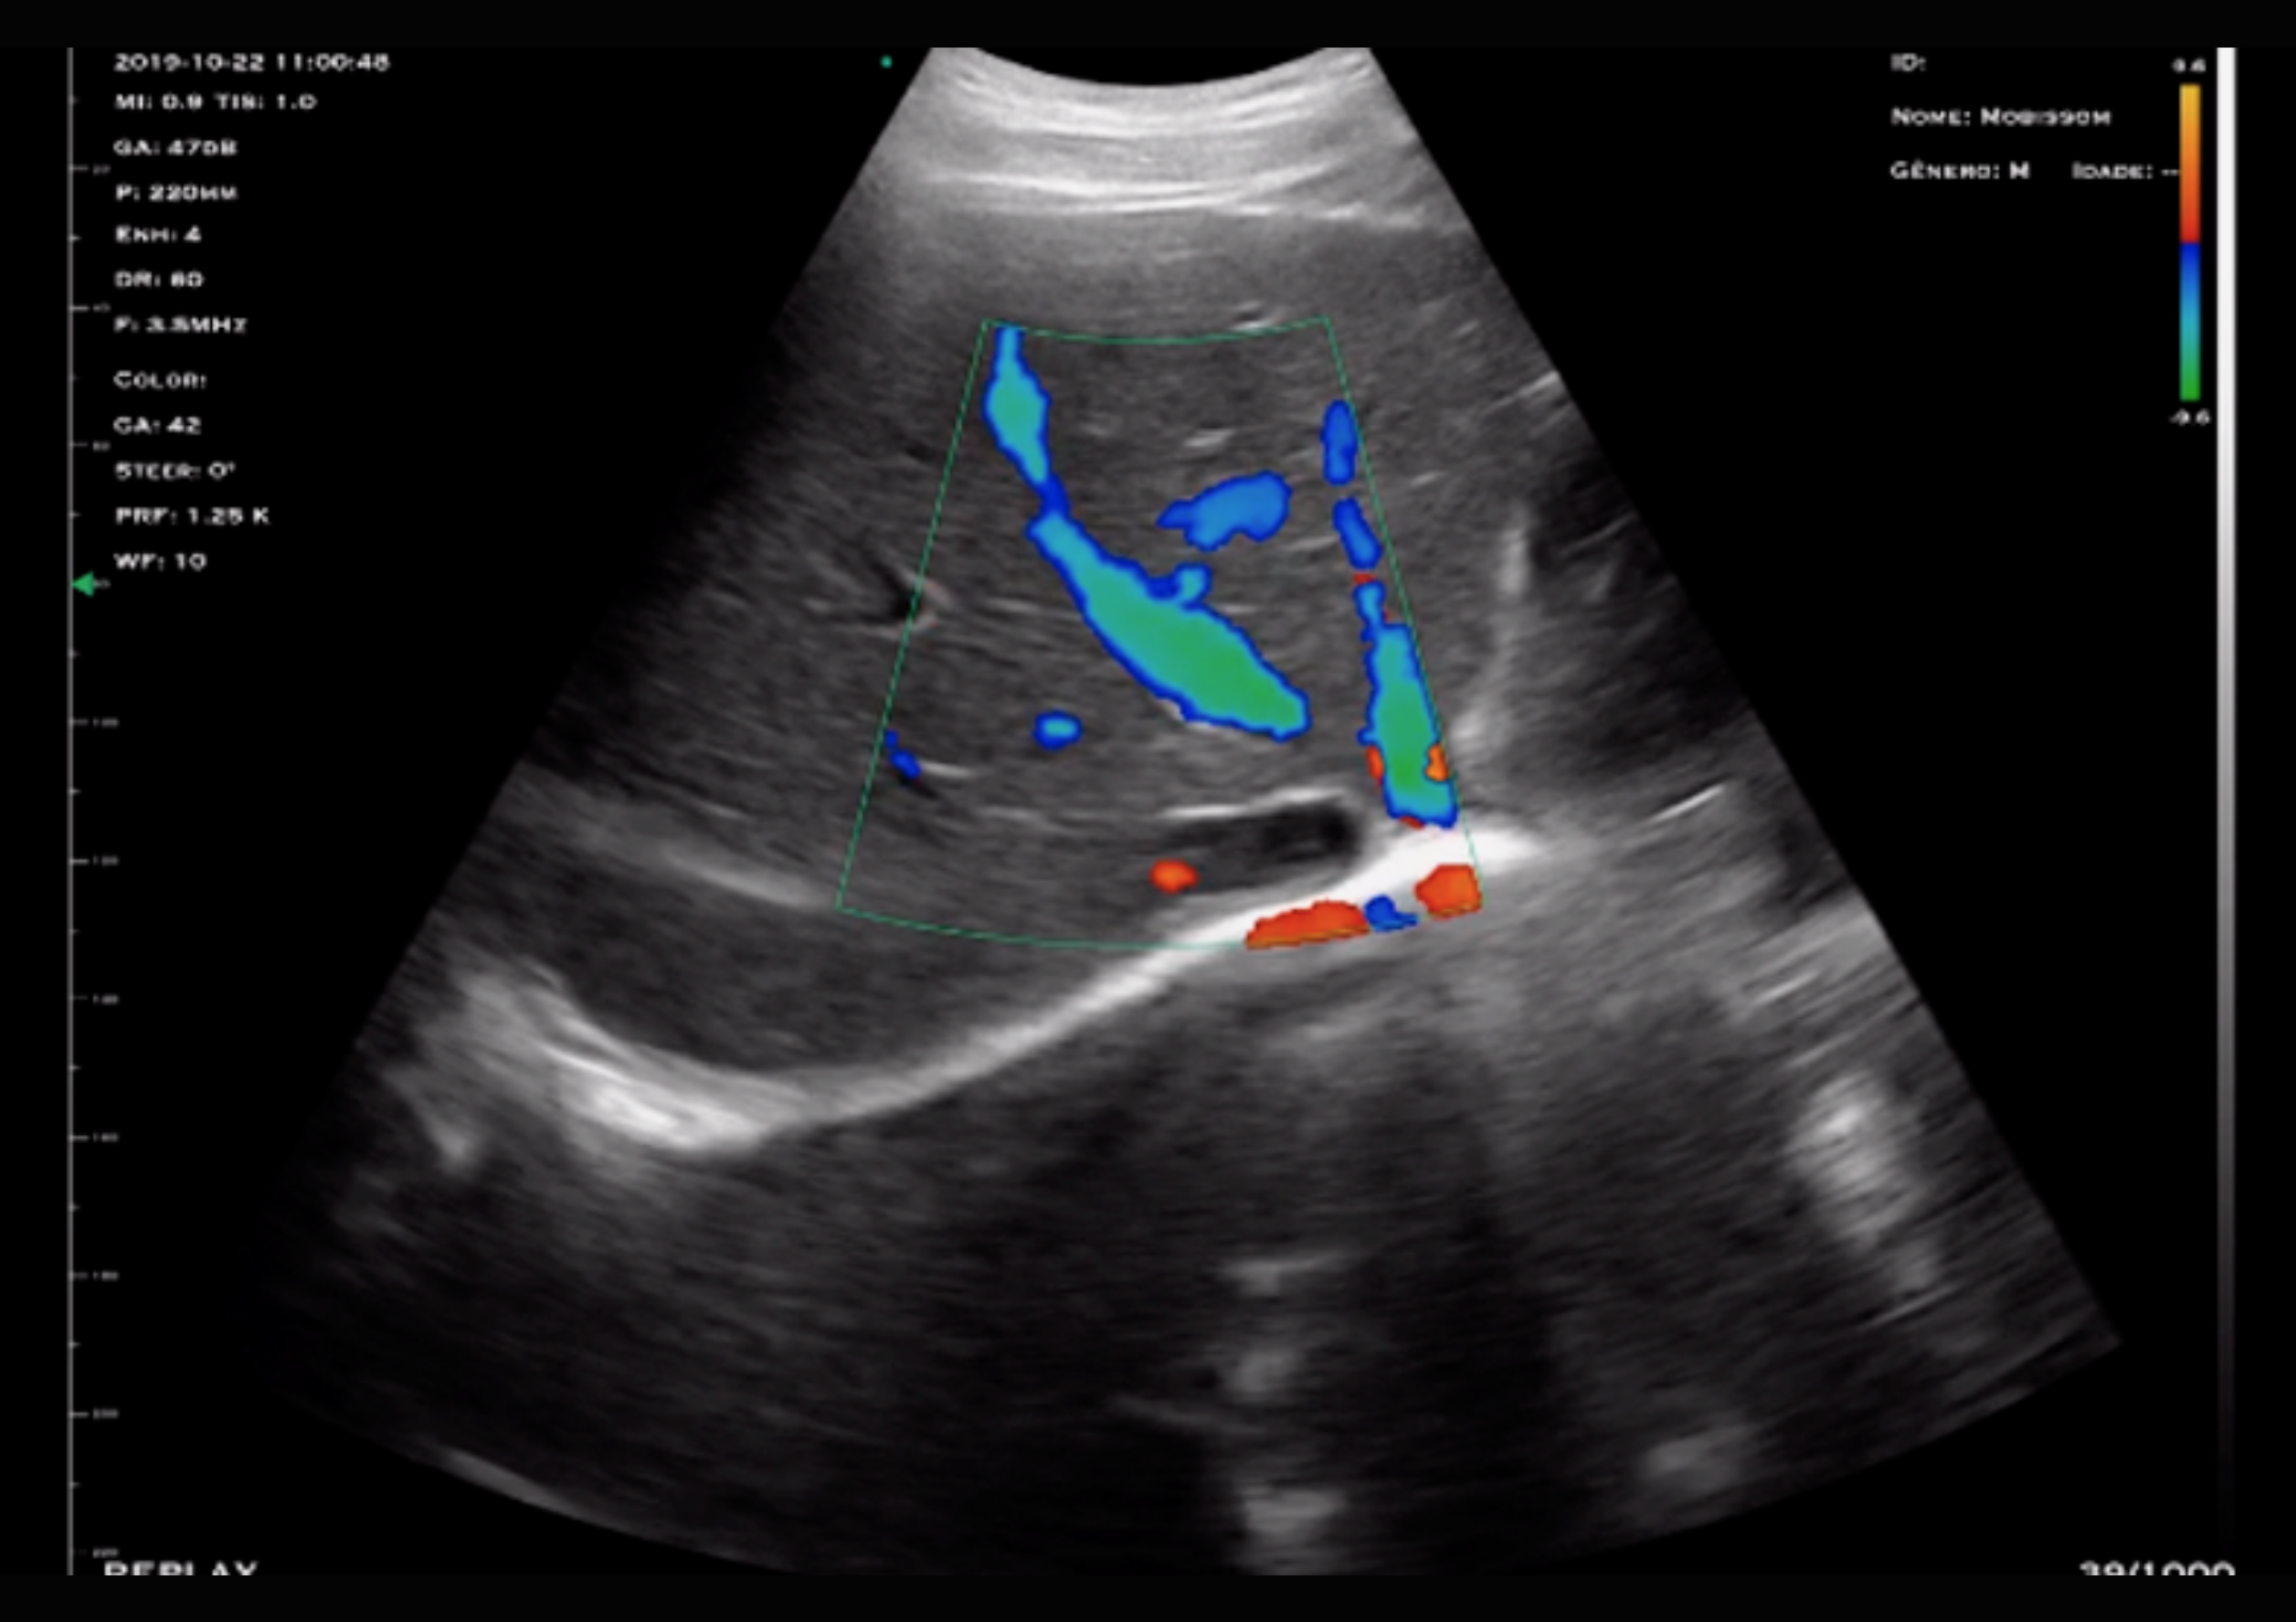

Composto por transdutores Linear e Convexo, o Mduo oferece alta versatilidade clínica. Suas frequências multifuncionais permitem atender a diferentes especialidades, com profundidade ajustável e modos de exame avançados como B, B/M, COLOR, PDI e PW.

Indicado para avaliação vascular arterial e venosa de membros periféricos, permitindo o diagnóstico e acompanhamento de trombose venosa profunda (TVP), identificação de varizes e avaliação da insuficiência venosa crônica.

Possibilita a avaliação de veias superficiais e profundas, bem como o estudo hemodinâmico por Doppler, auxiliando na definição terapêutica e no seguimento clínico.

Permite a avaliação das artérias carótidas e vertebrais, contribuindo para a análise de estenoses e alterações do fluxo.